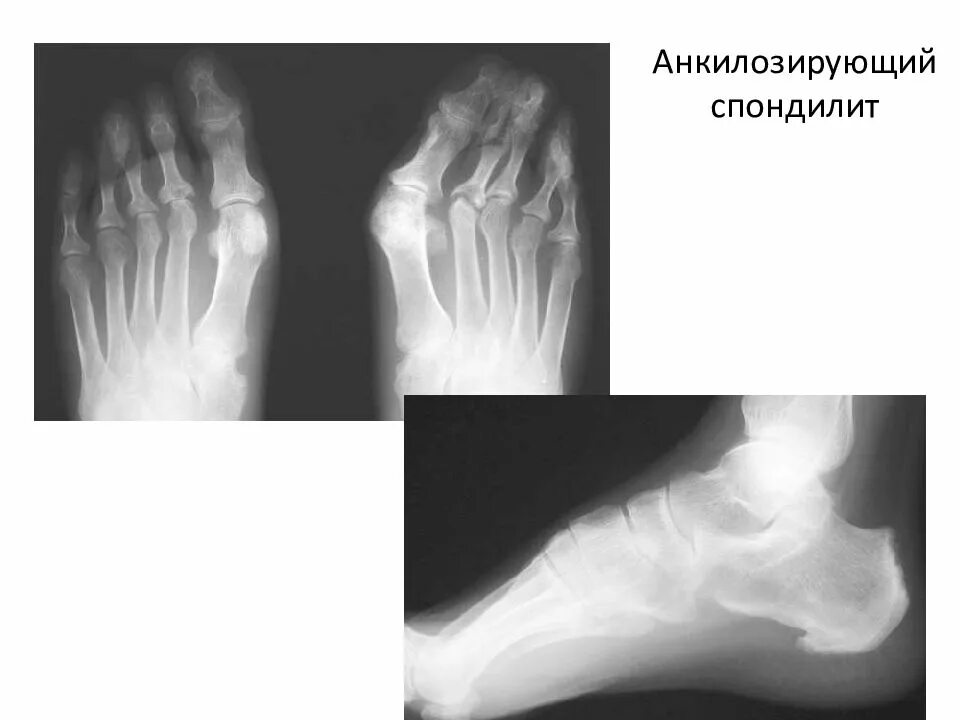

Болезнь бехтерева анкилозирующий